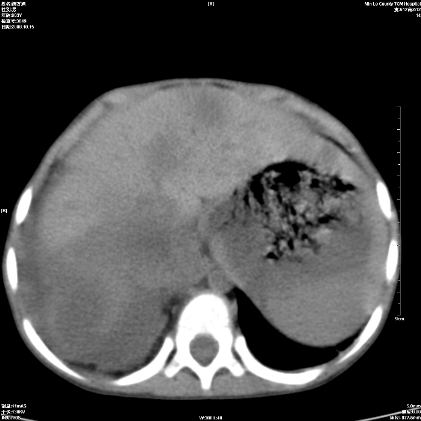

标题: PED1609:男性,3岁。彩超示肝Ca. [打印本页]

标题: PED1609:男性,3岁。彩超示肝Ca.

3岁;肝低密度灶;有钙化;有转移灶;考虑肝母细胞瘤;查afp

考虑后纵隔恶性畸胎瘤伴肝内多发转移可能性大,右侧肾上腺转移.

后纵隔恶性畸胎瘤,肝内多发转移可能性大,